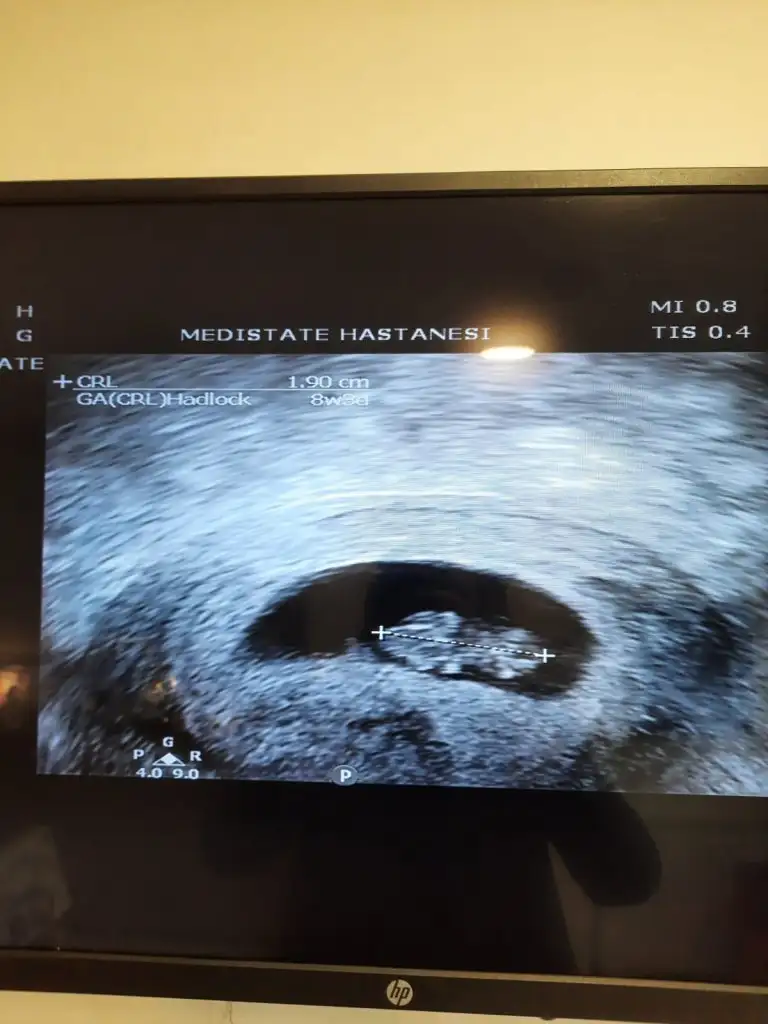

bu 7+4 den daha büyük canım emin misin 7+4 olduğuna7 hafta 4 günlük. Bana da söyler misin merak ettim.![]()

7+ 4 kesin ama doktor da çok büyük dedi hatta ikiz mi diye baya inceledi, sonra tek dedi. İnşallah kızdır Bi oğlum var Bi de kız olsun.bu 7+4 den daha büyük canım emin misin 7+4 olduğunabence kız

Evet bu da 7 haftalık görüntüsü.kız gibi duruyor canım 7 haftalık görüntüsü var mı?